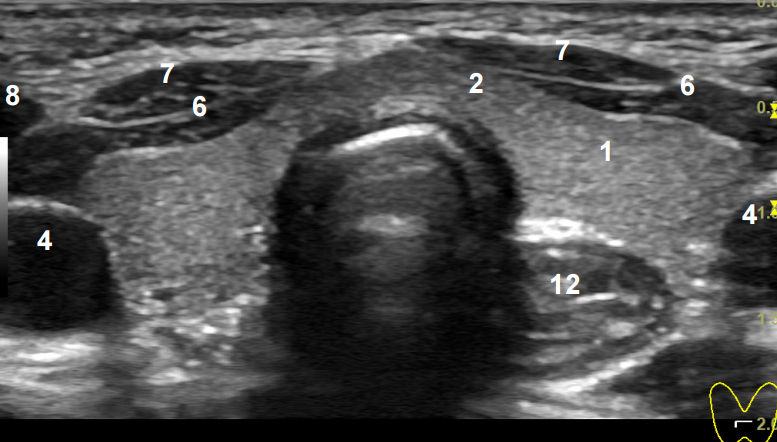

Еще один распространенный тест — УЗИ. Этот простой тест использует звуковые волны для визуализации щитовидной железы. Звуковые волны излучаются небольшим переносным датчиком, который проходит через щитовидную железу. На кожу наносится смазочный гель, чтобы звуковые волны легче передавались через кожу в щитовидную железу и окружающие структуры. Этот тест быстрый, точный, дешевый, безболезненный и полностью безопасный. Обычно это занимает всего около 10 минут, а результаты можно узнать практически сразу.Не все узелки нуждаются в этом тесте, но это почти обычная процедура.

Нужен ли мне тест?

На приведенном выше изображении показано ультразвуковое исследование типичного узла щитовидной железы, за исключением того, что этот узел немного больше обычного. Два скана идентичны, изображение справа обведено контуром, чтобы помочь вам понять, на что вы смотрите. Зонд помещается на кожу, которая находится в самом верху изображения, и звуковые волны направляются глубоко в шею и щитовидную железу (внизу изображения).

Когда звуковые волны ударяются о конструкции, они отражаются, как эхо. Зонд обнаруживает эти отражения и делает снимки. Этот узелок (показан красным) составляет около 80% ткани щитовидной железы (показана желтым цветом) в этой конкретной области щитовидной железы. Однако если вы посмотрите на другие части щитовидной железы, вы не увидите узелка; вы увидите только нормальную ткань щитовидной железы.

Определенные характеристики узлов щитовидной железы, видимые на УЗИ, вызывают большее беспокойство, чем другие.Однако имейте в виду, что одно только УЗИ не может диагностировать рак. Этот тест обычно помогает определить, что узелок имеет низкую вероятность злокачественного образования (имеет характеристики доброкачественного узла) или что он имеет некоторые характеристики злокачественного узелка, и поэтому показана биопсия.

Чтобы проиллюстрировать некоторые из этих моментов, на рисунке справа показан тот же ультразвук, что и выше, но на этот раз зонд запрограммирован на обнаружение кровотока .Теперь вы можете ясно видеть, что этот узел сложный, что означает, что некоторые из них кистозные, а другие части состоят из живых тканей, которые имеют хорошее кровоснабжение. Если бы это была простая киста, заполненная серозной жидкостью, то в ней не было бы красного (артерия) или синего (вена) кровотока.

У этой пациентки не было других узелков в щитовидной железе, поэтому был поставлен диагноз «доминантный комплексный узел правой доли щитовидной железы».

Поскольку этот узелок действительно имеет несколько вызывающих беспокойство характеристик, была проведена пункционная биопсия тонкой иглой (FNA).В этом тесте очень маленькая игла вводится в узелок, некоторые клетки отсасываются, а затем помещаются на предметное стекло, чтобы патологоанатом окрасил их и определил, являются ли они злокачественными.